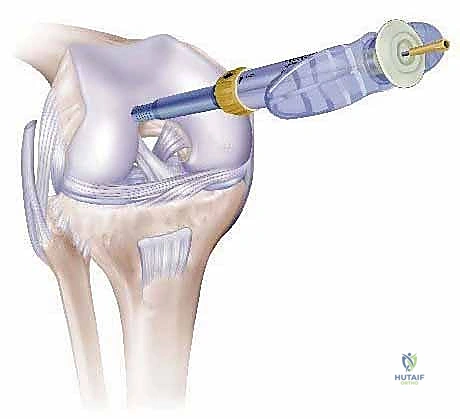

This is where the COR osteochondral repair system shines, allowing for precise harvesting.

- Graft Harvesting (Using COR System):

- Surgical Directive: "Nurse, prepare the COR system harvester, 6mm diameter, set to 12mm depth."

- Technique:

- "We position the harvester precisely over the selected donor site. The COR system's 'perpendicularity' guide is invaluable here. We must ensure the harvester is perfectly perpendicular to the articular surface. Any angulation will result in an elliptical or beveled plug, leading to a poor fit and compromised integration."

- "Under direct arthroscopic visualization, I'm gently advancing the harvester. The goal is a smooth, controlled cut, capturing a full-thickness cylinder of healthy cartilage, the tidemark, and an adequate amount of subchondral bone."

- "Feel for the tactile feedback as the harvester engages the bone. Once the desired depth is reached, we carefully extract the plug."

- Surgical Warning:

> "Avoid any rotational forces during extraction that could shear the cartilage from the bone. The plug should be removed cleanly, preserving chondrocyte viability." - "Once harvested, the plug is immediately transferred to a sterile holding solution to maintain chondrocyte viability while we prepare the recipient site."

- Clinical Pearl: The COR system aims for a precise, same-length plug and recipient hole, minimizing impact forces and optimizing cell survival, which is a key advantage.